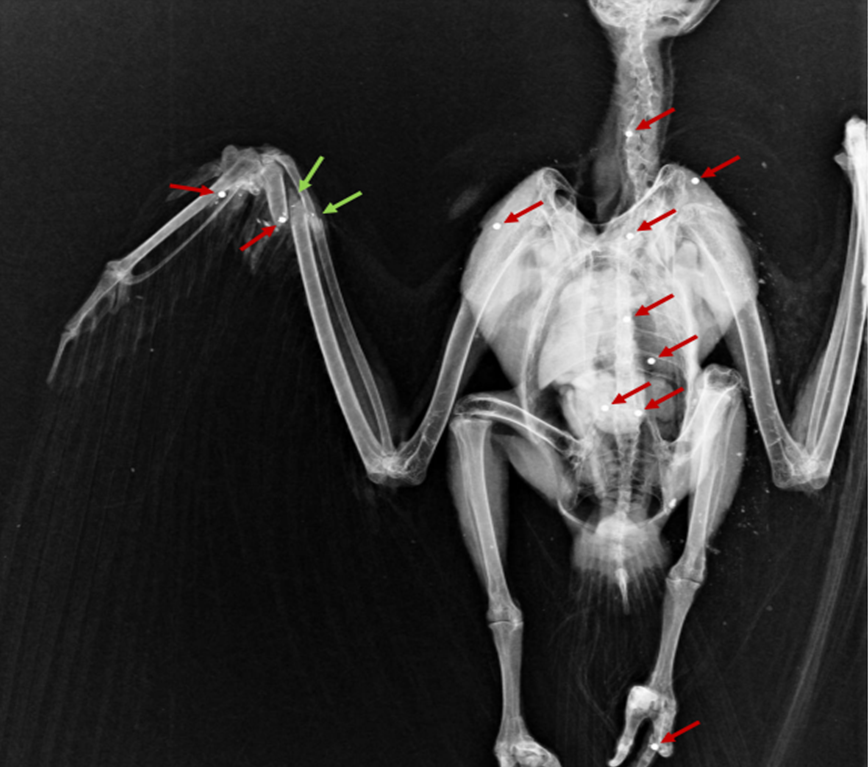

Como se pode ver no raio-x, o animal tinha 11 chumbos (setas vermelhas) alojados por todo o corpo, e 2 fracturas (setas verdes) na asa direita provocadas pelos mesmos. Na necropsia foi ainda possível observar lesões de um chumbo que atravessou o animal na cabeça, tendo entrado pelo palato e saído pelo crânio. Eram ainda evidentes lesões no coração e no fígado.